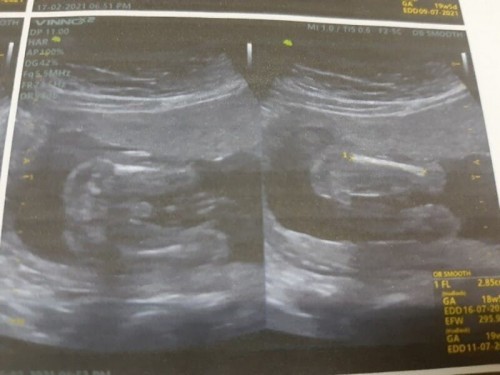

ตื่นเต้นมาก ก่อนไปซาวด์ได้ทำการคุยและตกลงกับหนูน้อยว่าขอให้หนูไม่หนีบไม่เอามือบังนะคะ คุณพ่ออยากเห็น ดีนะที่หนูน้อยเป็นเด็กดี เลยได้เห็นเพศและหน้า ได้ลูกชายสมใจคุณพ่อเค้าล่ะ คุณแม่เดือน ก.ค. ได้ลูกชายหรือลูกสาวกันบ้างคะ มาอวดกันหน่อย #ท้องแรกค่ะ 19+6 week

ผลตรวจนิฟตี้ออกมาแล้วตอน15week ในรูปซาวน์19weekชัดแจ่มแจ๋ว ไม่ต้องกลัวหดเลยค่ะ#ทีมลูกชายสมใจแม่